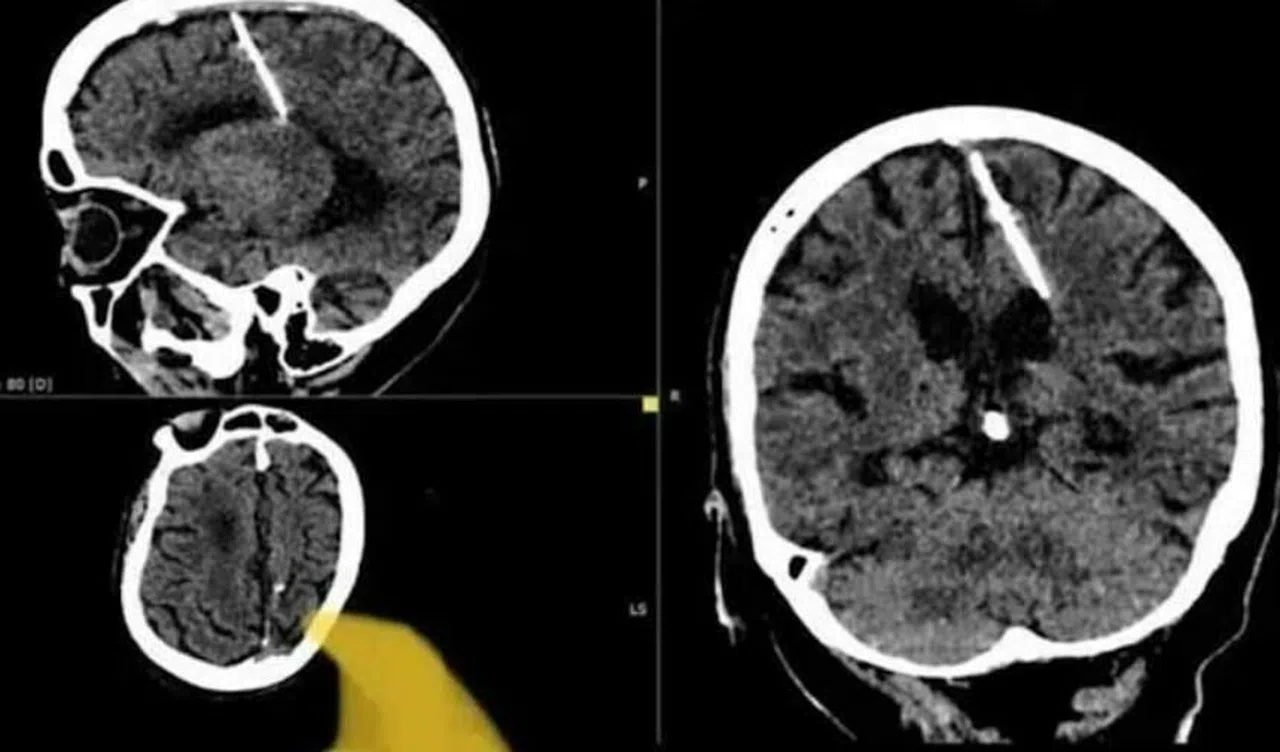

Rusya'nın doğusundaki yaşlı bir kadının, beyninde 3 cm uzunluğunda bir iğne ile 80 yıl boyunca yaşadığı, doktorların tarafından ortaya çıkarıldı.

Rusya'nın doğusundaki bir 80 yaşındaki kadının beyninde 3 cm uzunluğunda bir iğne taşıdığı, bu ilginç durumun doktorlar tarafından keşfedildiği ortaya çıktı. Kadının bu olaya nasıl maruz kaldığı ise dikkat çekici bir hikayeye dayanıyor.

Sakhalin bölgesi sağlık yetkilileri, kadının ebeveynleri tarafından gerçekleştirilen başarısız bir çocuk düşürme girişimi sonucu bu durumun ortaya çıkmış olabileceğini düşünüyor. Bu trajik dönemde Sovyetler Birliği'nde gıda kıtlığı yaygınken, birçok insan zorlu ekonomik koşullar altında yaşıyordu.

Sağlık departmanı yetkilileri, "İğne sol parietal lobuna girdi, ancak amaçlanan etkiyi yaratmadı; kız hayatta kaldı" dedi. Hastanın şaşırtıcı bir şekilde iğnenin neden olduğu bir baş ağrısından veya başka bir sağlık sorunundan şikayet etmediği belirtildi. Durumu şu an ilgili bir doktor tarafından yakından izleniyor.